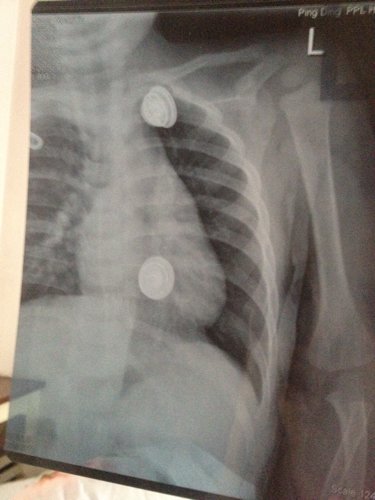

一岁半宝宝从写字台上掉下'诊断结果为左锁骨中段青枝骨折。请问'愈合需要多长时间'需注意什么。会不会留下什么后遗症。饮食上需要补吗?

病情分析: 这种情况是青枝植骨没有完全断裂,可以完全恢复的。而且愈合很快。 指导意见: 建议局部充分制动,可以做一下上肢的悬吊固定关节避免活动,一般半个月可以愈合恢复。没有后遗症。